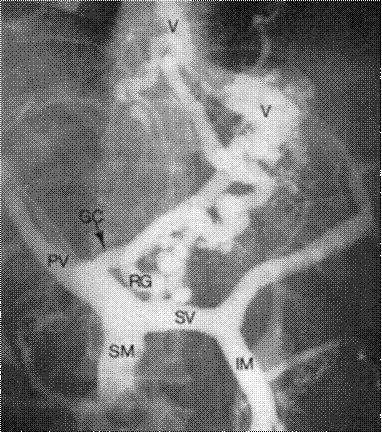

—  Портограмма (PV - воротная вена, SV - селезеночная вена, SM - верхняя брыжеечная вена, IM - нижняя брыжеечная вена, RG - правая вена желудка, GC - коронарная вена желудка, V - варикоз вен кардии и пищевода)